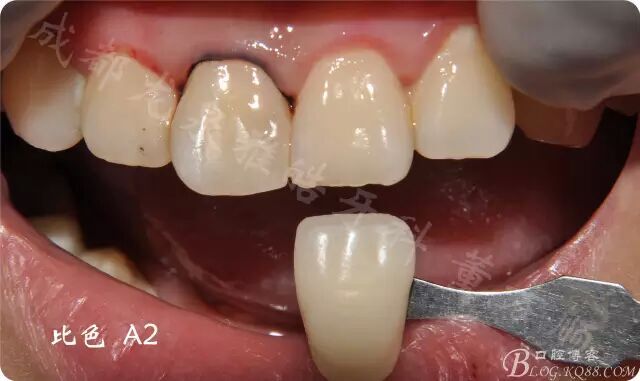

比色

遠中鄰面 預(yù)備過渡到自潔區(qū) 與牙體長軸呈L型(圖片由于相機曝光調(diào)了 不是很自然)